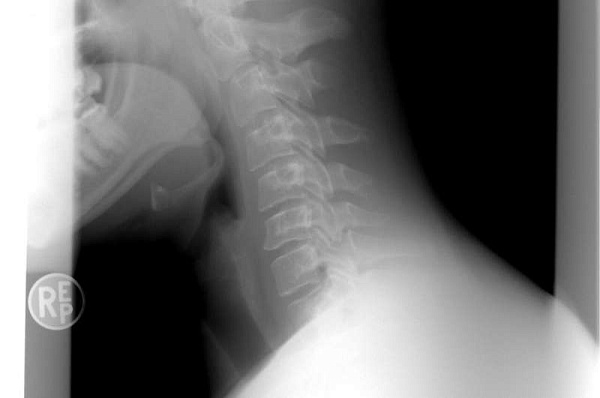

Новое устройство определяет шейную патологию по движению пальцев

Метод, разработанный учёными, основан на комбинации машинного обучения и анализа движений пальцев с помощью бесконтактного датчика. Технология была протестирована на пациентах с шейной миелопатией: участники совершали захваты пальцами, а устройство считывало, насколько трудно им это делать.

Бесконтактный сенсор, позволяющий измерять движения пальцев, называется Leap Motion. Учёные подключили это устройство к ноутбуку, а затем попросили пациентов как можно быстрее согнуть и разогнуть пальцы 20 раз. Движения отображались на экране ноутбука, а также записывались в качестве данных. Всего в испытаниях участвовало 78 добровольцев, имеющих и не имеющих шейную миелопатию.